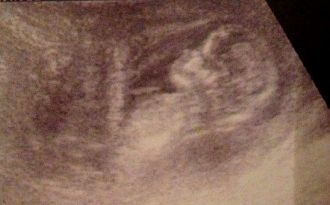

Echo 12ème semaine

Le 11 Février 2013. Ton papa me téléphone a 7h30 du matin pour me dire qu'il a beaucoup neigé cette nuit ( tombé 30cm ) et qu'il faut repousser le rendez-vous à un autre jour car il nous faut faire 40km pour te voir...

Pour ta maman il est or de question de louper ce moment donc convint ton papa pour venir avec elle, même s'il faut mettre 2h pour arriver chez Mme le gynécologue.

Ta maman fait le nécessaire pour prévenir de notre retard et après avoir roulé à 50km/h, nous sommes enfin arrivés à destination...

Ta maman se souviendra toute sa vie le moment où ta frimousse s'est mis en place sur l'écran, les larmes sont montées et son cœur s'est emballé, d'un embryon tu es devenu un véritable bébé avec un profil magnifique...

Mme la gynécologue est très rigolote et partage tout tes mouvements que je ne sens pas encore, en me disant " vous voyez il s'est retourné..."

Ton papa est aussi ému que moi mais essayons de garder notre dignité devant le médecin...

Nous devons prendre rendez-vous pour la mesure de ta nuque et savoir enfin si tu seras un ou une merveille !!